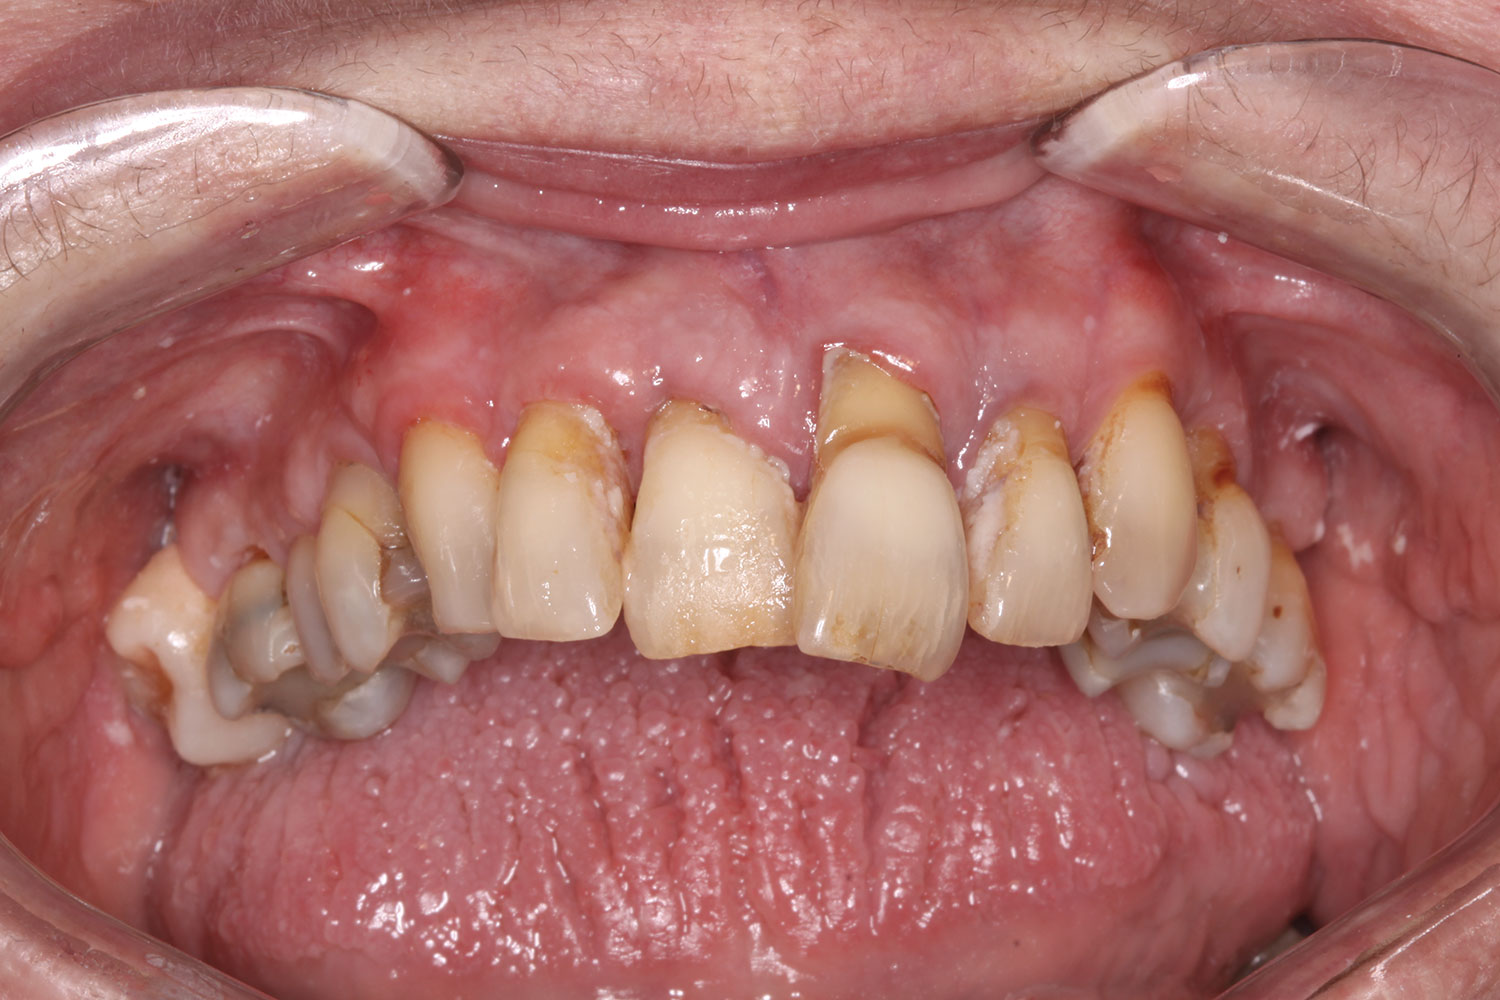

A 60-year-old female patient presented with many periodontally and restoratively hopeless teeth that severely compromised esthetics and function and were inadequate to retain a maxillary restoration. She declined to advance into a full maxillary denture or partial denture. Existing maxillary teeth included Nos. 2 and 4 through 14 (Figure 9 and Figure 10). The opposing dentition was stable. The patient was in good health with no allergies to medication.

Fig 9. Case 2: Initial presentation for maxillary immediate implant, immediate load provisional restoration. Full-face photograph.

Fig 10. Initial clinical situation, intraoral view.